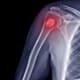

Bones are built somewhat like PVC pipes – there is a thick outer cortex that gives bone strength with the inside filled with spongy bone marrow. When cancer spreads to the bone, it can create weak points or holes in the cortex that lead to fractures. Prophylactic stabilization can help prevent fractures before they occur.

Your orthopaedic oncologist can reinforce the bone using implanted hardware such as rods, plates, screws, and/or cement. The surgeon may need to replace a portion of the bone with metal in the form of a joint replacement surgery.